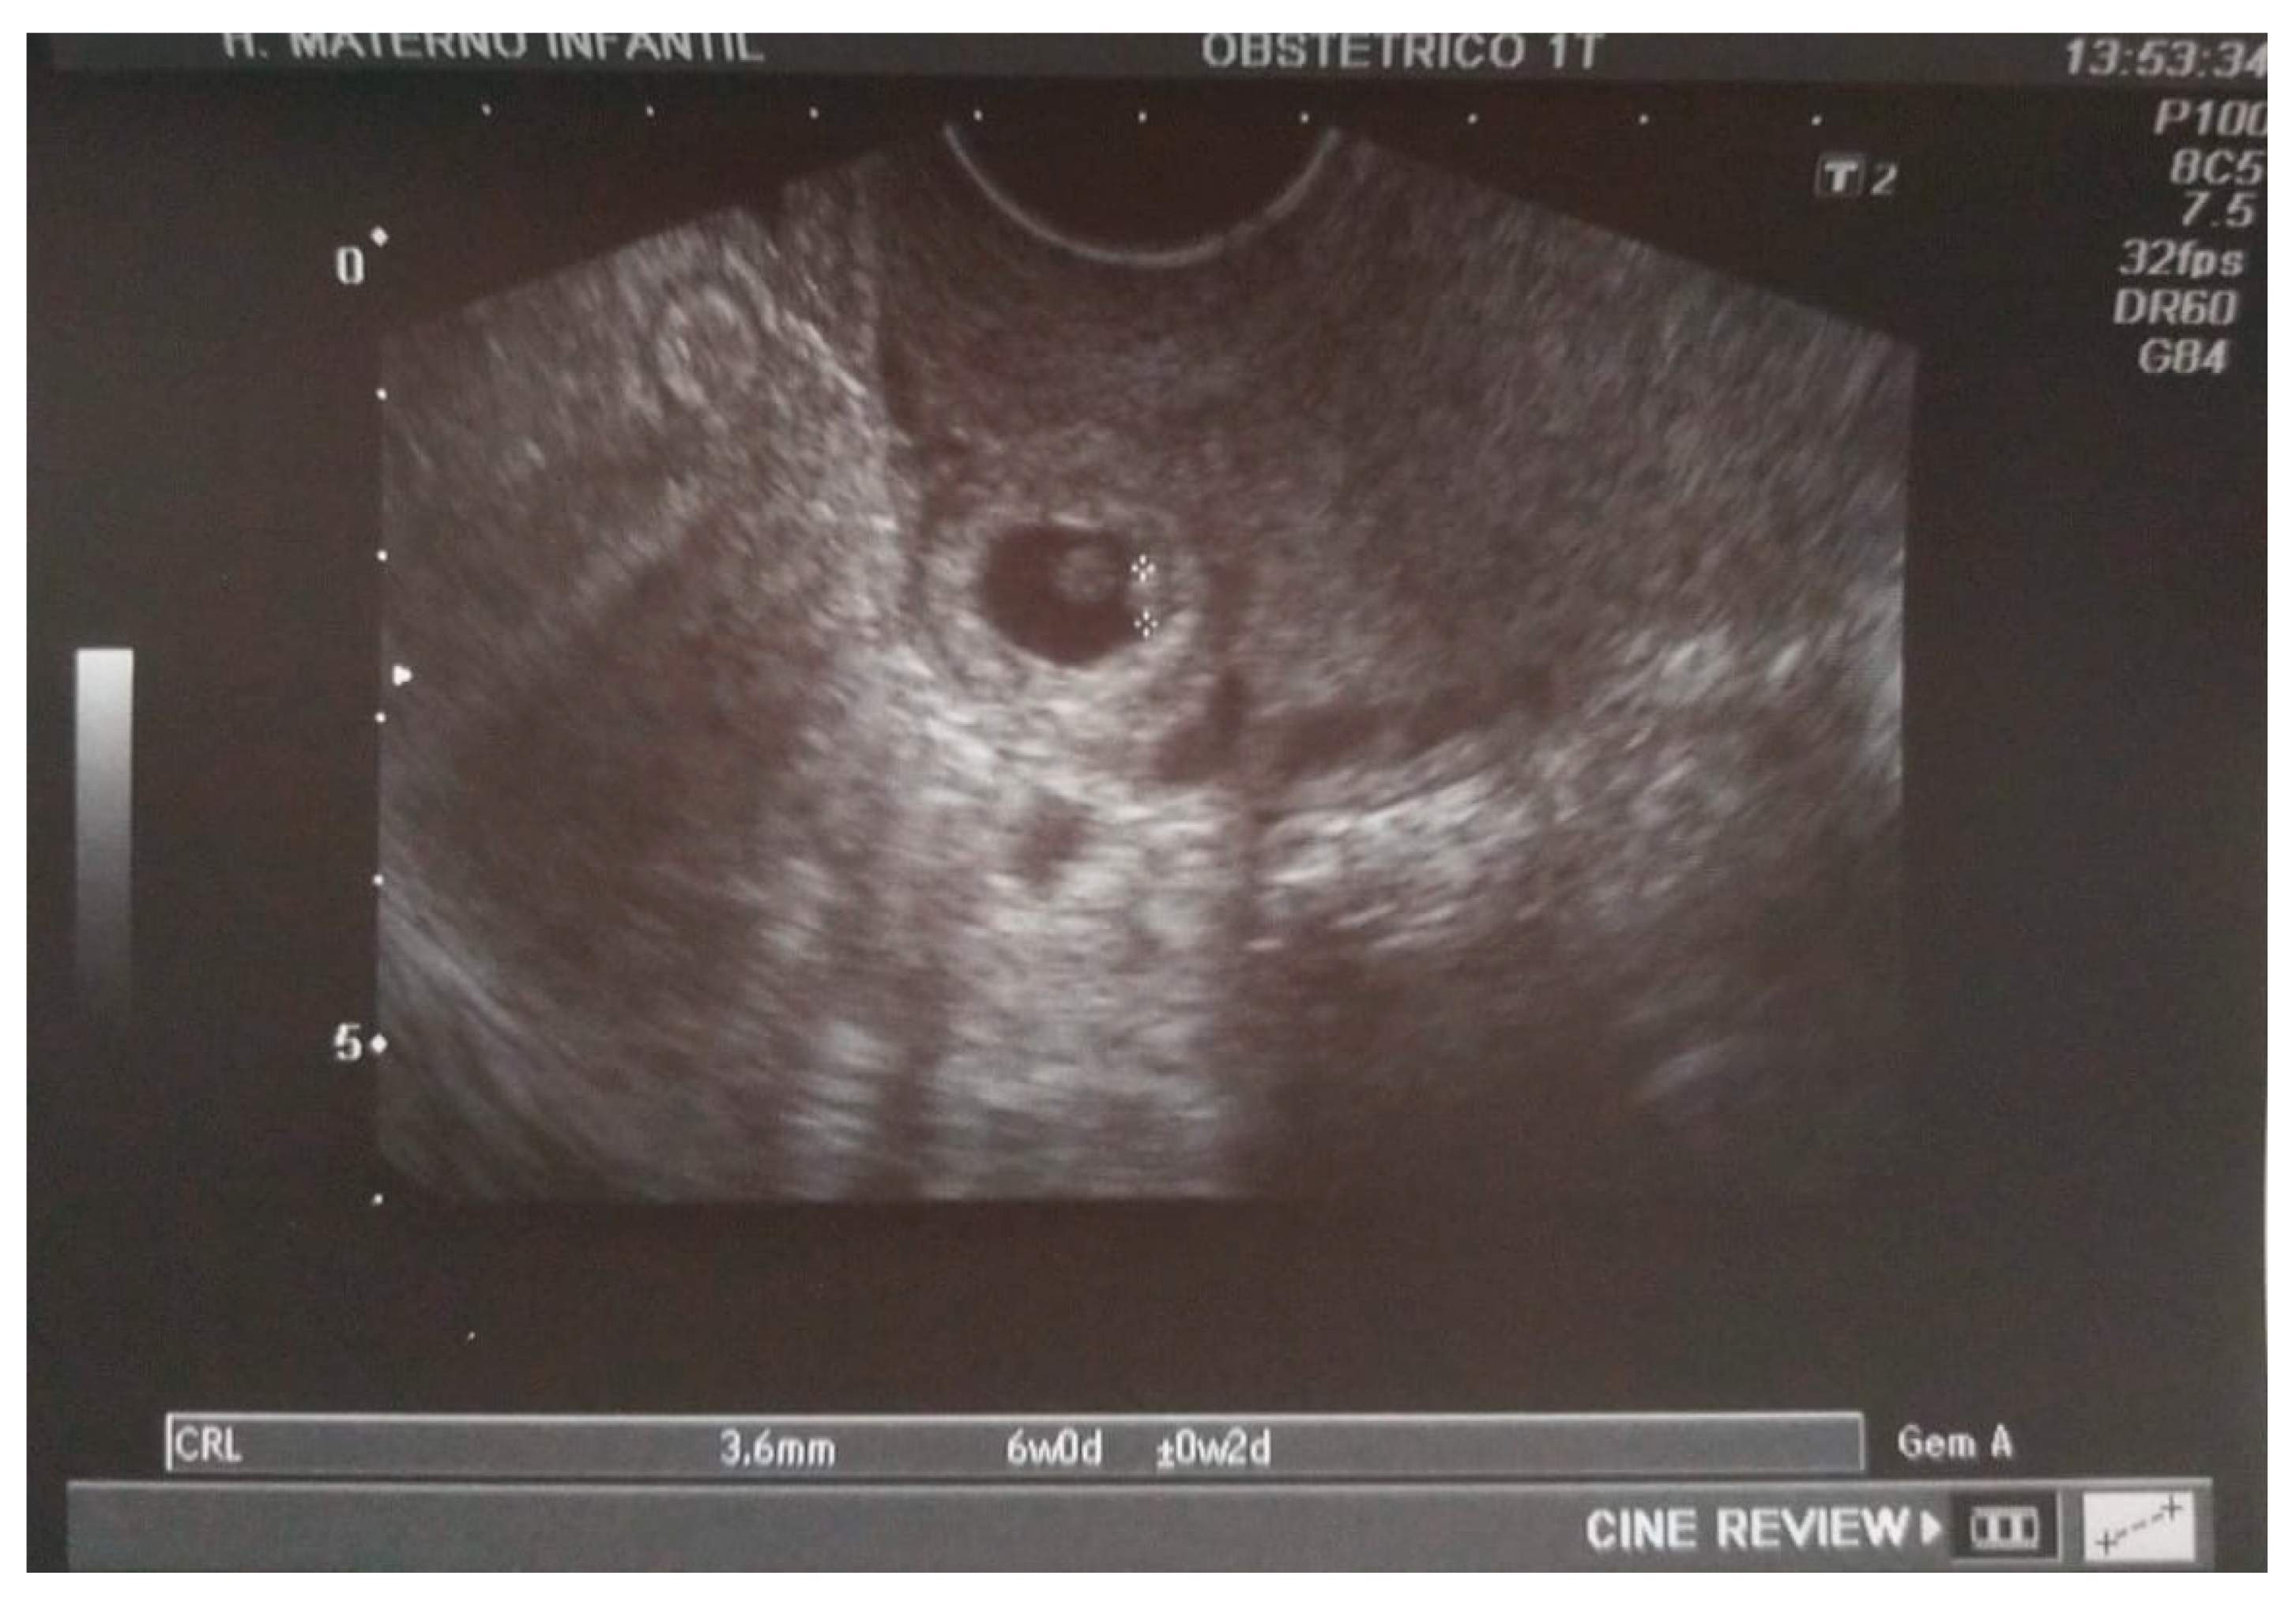

A transvaginal ultrasound was performed (Figure 2), revealing a retroflexed uterus with endomyometrium measuring 6 mm, a gestational sac of 15 mm, and an embryo of 3.6 mm with positive cardiac activity located on the cesarean scar. The bladder was not invaded, and there was normal adnexal and a small amount of free fluid in the pouch of Douglas. The patient’s serum determination of betahCG was 14,508 UI/L.

Figure 2. A sagittal transvaginal image showing a gestational sac implanted in the scar area of the previous cesarean with a 3.6 mm embryo.